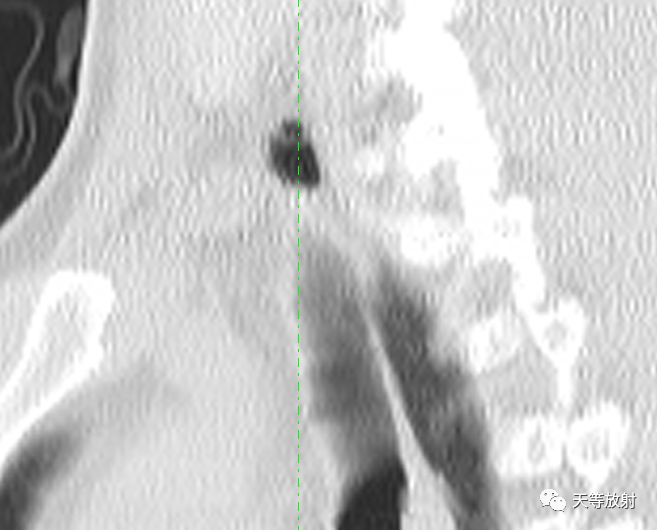

冠状位及矢状位观察,囊影位于胸廓入口右侧旁。